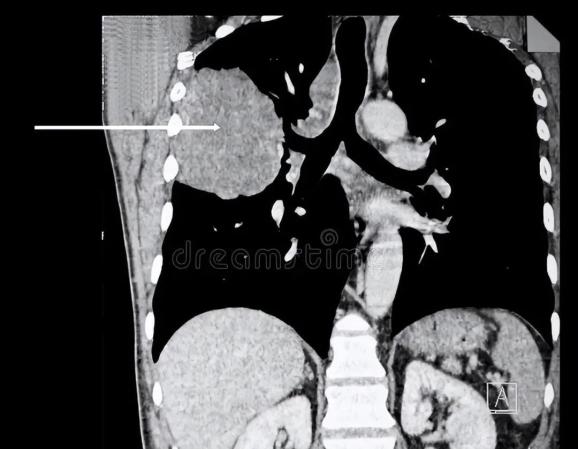

2.确诊困难

脑膜转移患者临床表现缺乏特异性,有时候会误认为是其他神经系统问题,一般来说,增强MRI是发现脑实质转移病灶的首选影像检查。但脑膜转移有时在增强磁共振中没有任何发现,确诊需要进行腰椎穿刺,抽脑脊液检查,脑脊液中找到恶性肿瘤细胞才可以确诊。